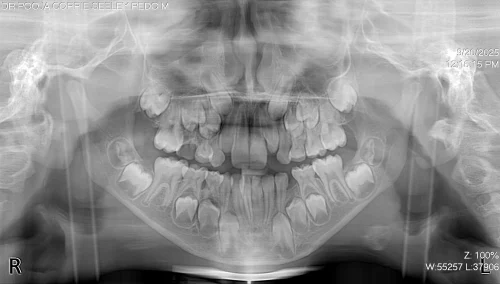

The complete clinical and radiographic evaluation, to include Orthopantomogram (OPG), exposed severe crowding of the lower anterior area, as well as premature loss of the lower left primary molar (#L), which leads to loss of space and causes the permanent teeth to migrate mesially. This diagnosis was sufficiently clear enough to result in the insertion of a fixed lingual holding arch with U loops to ensure space and support the symmetry of the arch until a natural eruption of successors.